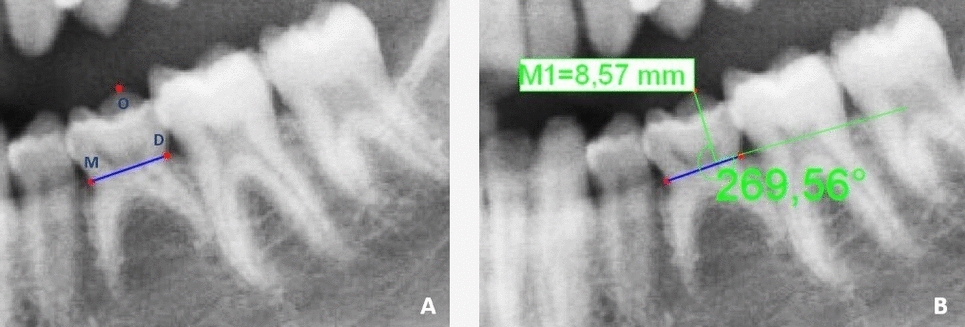

Unal Erzurumlu Z, Sadik E, Gokkurt BN, Ozbey F, Erzurumlu K, Kasko Arici Y. Morphological evaluation of gonial and antegonial regions in bruxers on panoramic radiographic images. BMC Oral Health. 2023;23(1):457. https://doi.org/10.1186/s12903-023-03162-0.

Kurt MH, Yilmaz S, Evli C, Karahan S. Comparative evaluation of trabecular bone structures of bruxist and non-bruxist individuals with bone apposition in the mandible angle region by fractal analysis. J Oral Rehabil. 2023;50(5):360–9. https://doi.org/10.1111/joor.13435.

Gulec M, Tassoker M, Ozcan S, Orhan K. Evaluation of the mandibular trabecular bone in patients with bruxism using fractal analysis. Oral Radiol. 2021;37(1):36–45. https://doi.org/10.1007/s11282-020-00422-5.